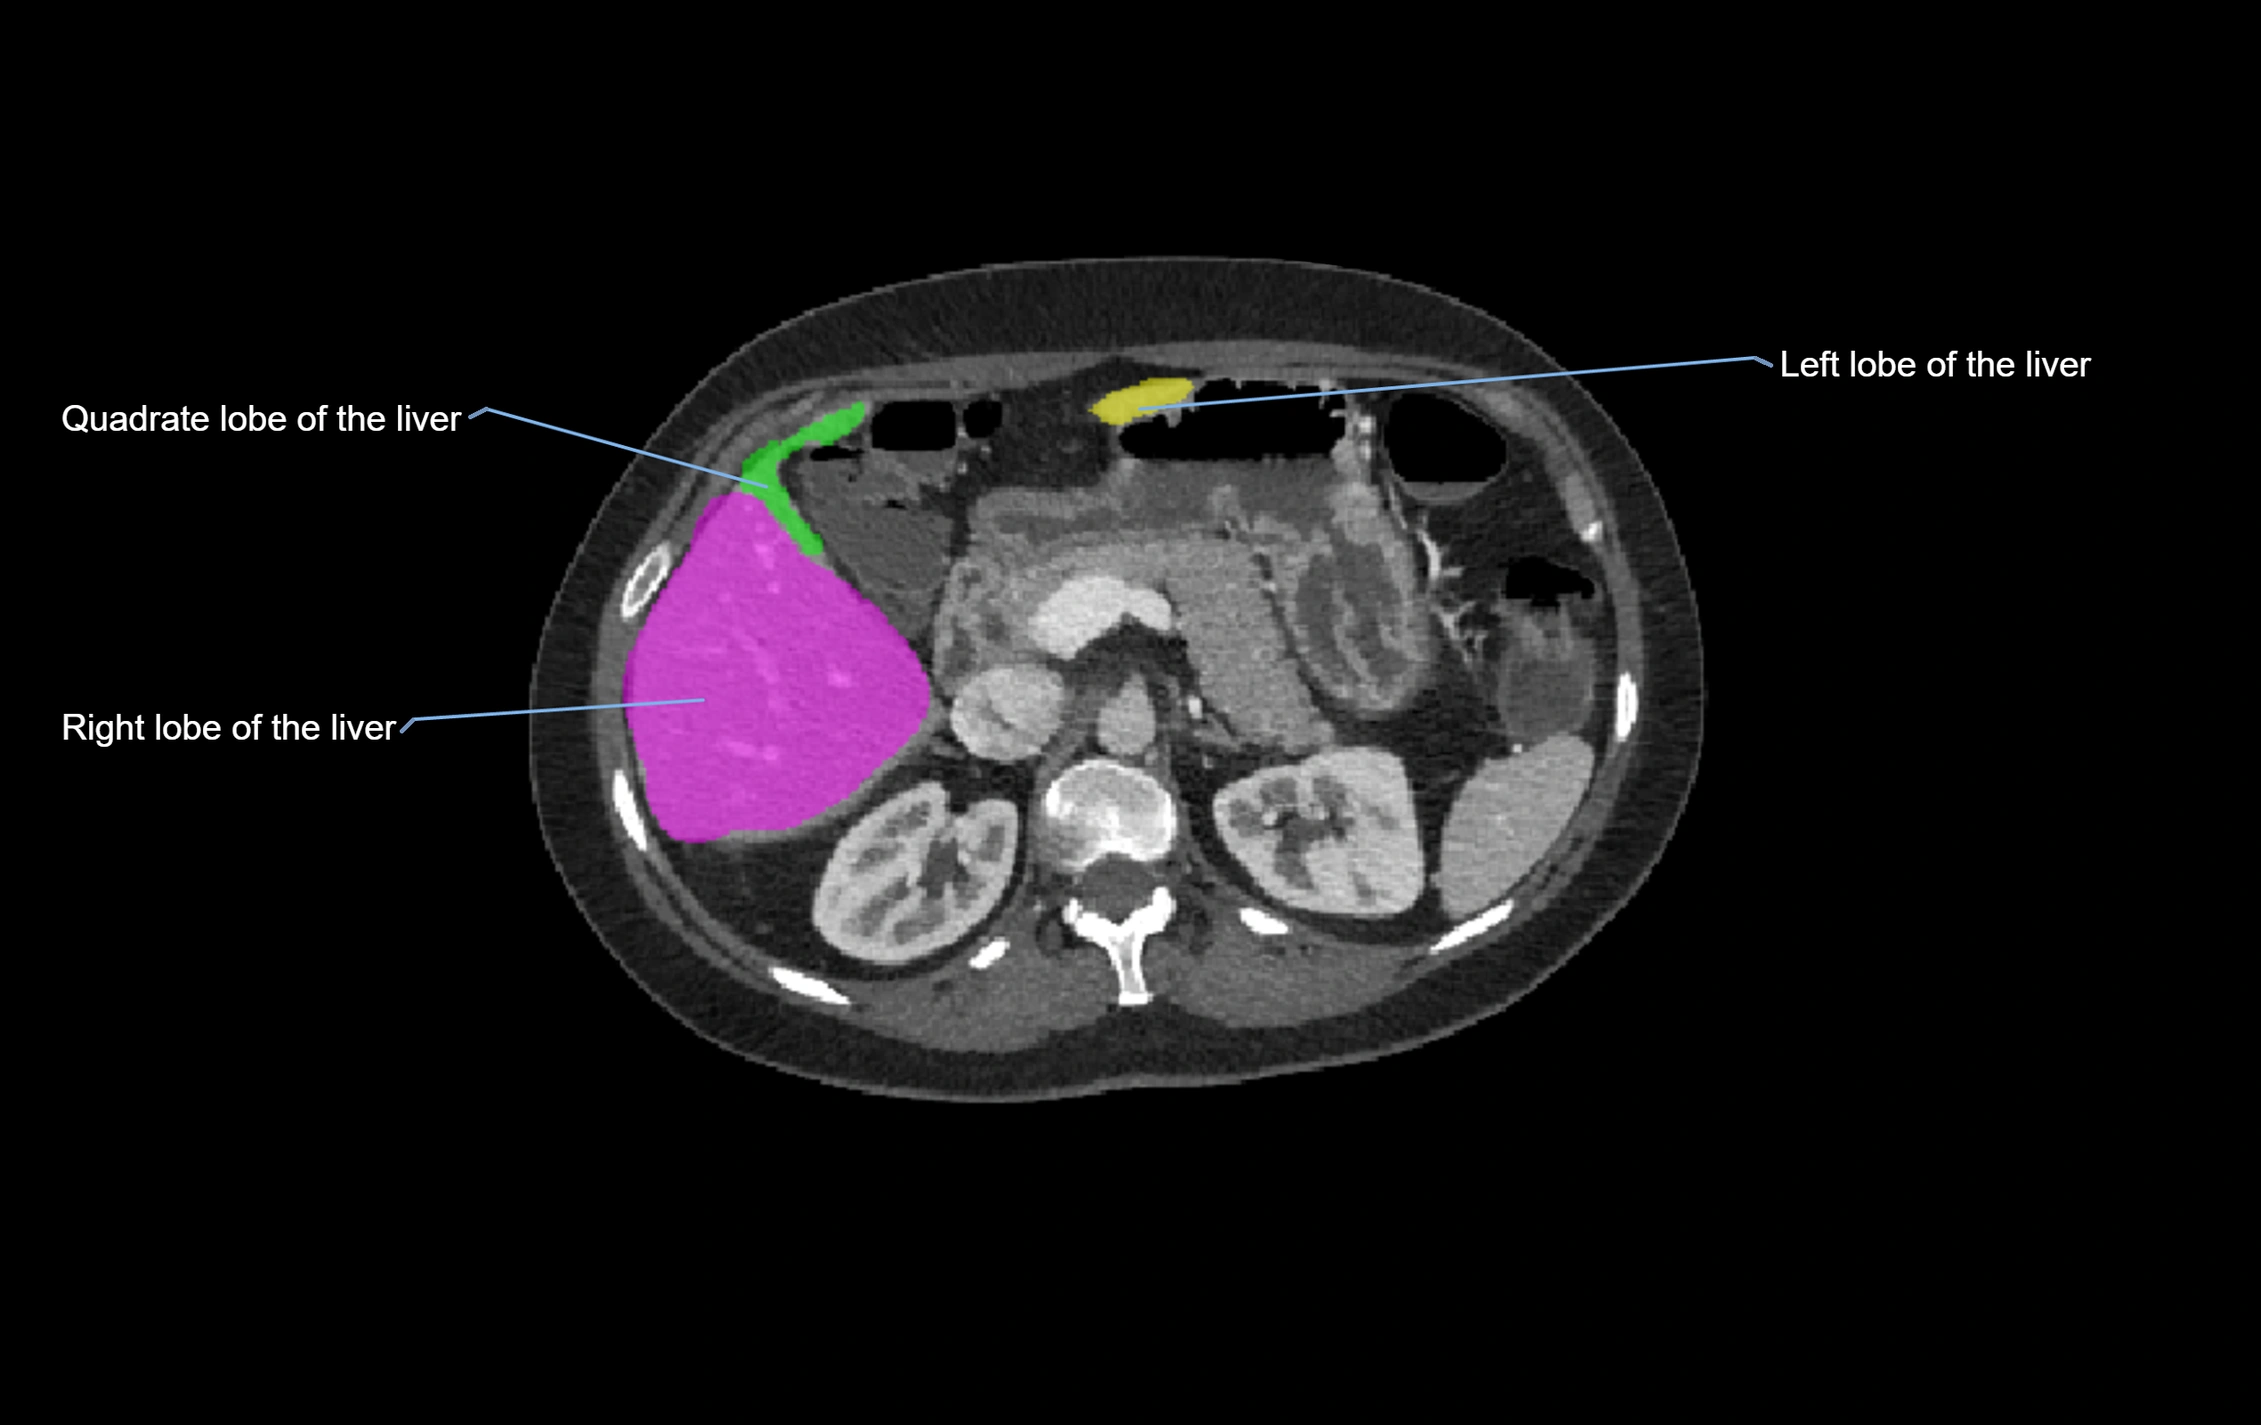

CT Appearance

CT Pre-Contrast:

• Caudate lobe appears as a soft-tissue density, isodense to the rest of the liver

• Enlargement may be appreciated in cirrhosis or Budd–Chiari syndrome

CT Post-Contrast:

• Homogeneous enhancement in the portal venous phase, similar to rest of liver

• Independent venous drainage into the IVC may be visualized

• Lesions follow characteristic CT enhancement patterns (HCC: arterial hyperenhancement with washout; hemangiomas: peripheral nodular enhancement with centripetal fill-in)

CT Venous Phase (functional significance):

• Caudate lobe often enhances relatively more than other lobes in Budd–Chiari syndrome, due to preserved venous outflow